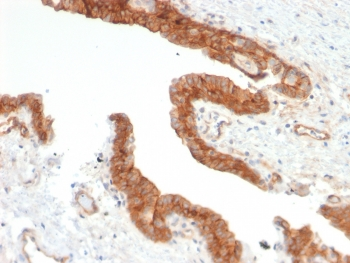

IHC staining of FFPE human colon carcinoma with CD73 antibody (clone NT5E/2545). HIER: boil tissue sections in pH9 10mM Tris with 1mM EDTA for 10-20 min and allow to cool before testing.